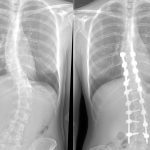

Сколиоз 4 степени

Самой тяжелой формой является сколиоз 4 степени (фото 5), когда искривление заметно окружающим. Лечение требует серьезных мер. Чаще всего сколиоз 4 степени исправляется только оперативным путем. У пациента, имеющего с-образный сколиоз, спина в буквальном смысле согнута в одну из сторон. Изгиб обычно более 50 градусов. 4 стадия сколиоза формируется при игнорировании лечения 3 стадии.

Правосторонний или левосторонний грудной сколиоз опасен тем, что меняется не только скелет, но и органы. Могут начаться проблемы с ЖКТ и легкими. Также имеется риск перехода в условный сколиоз 5 степени. Такого рода сколиоз у детей бывает редко. Взрослый человек наиболее подвержен этому виду.

В 4 стадии сколиоз шейного отдела позвоночника вместе с грудным и поясничным, представляют собой полностью искривленную спину в форме буквы S. Такие нарушения наблюдались вследствие внутренних изменений организма. К тому же, шейный сколиоз приводит к патологиям важных органов.

Не стоит рассматривать кифоз позвоночника, как разновидность сколиоза. Это явление называется сутулостью. Сколиоз позвоночника (фото 6) легко отличить, пройдя медицинский тест. Бывает левосторонний и правосторонний сколиоз, в зависимости от стороны искривления. Возникает в грудном или спинном отделе. В любой форме заболевание необходимо лечить в срочном порядке, сколиоз до и после операции значительно отличается.